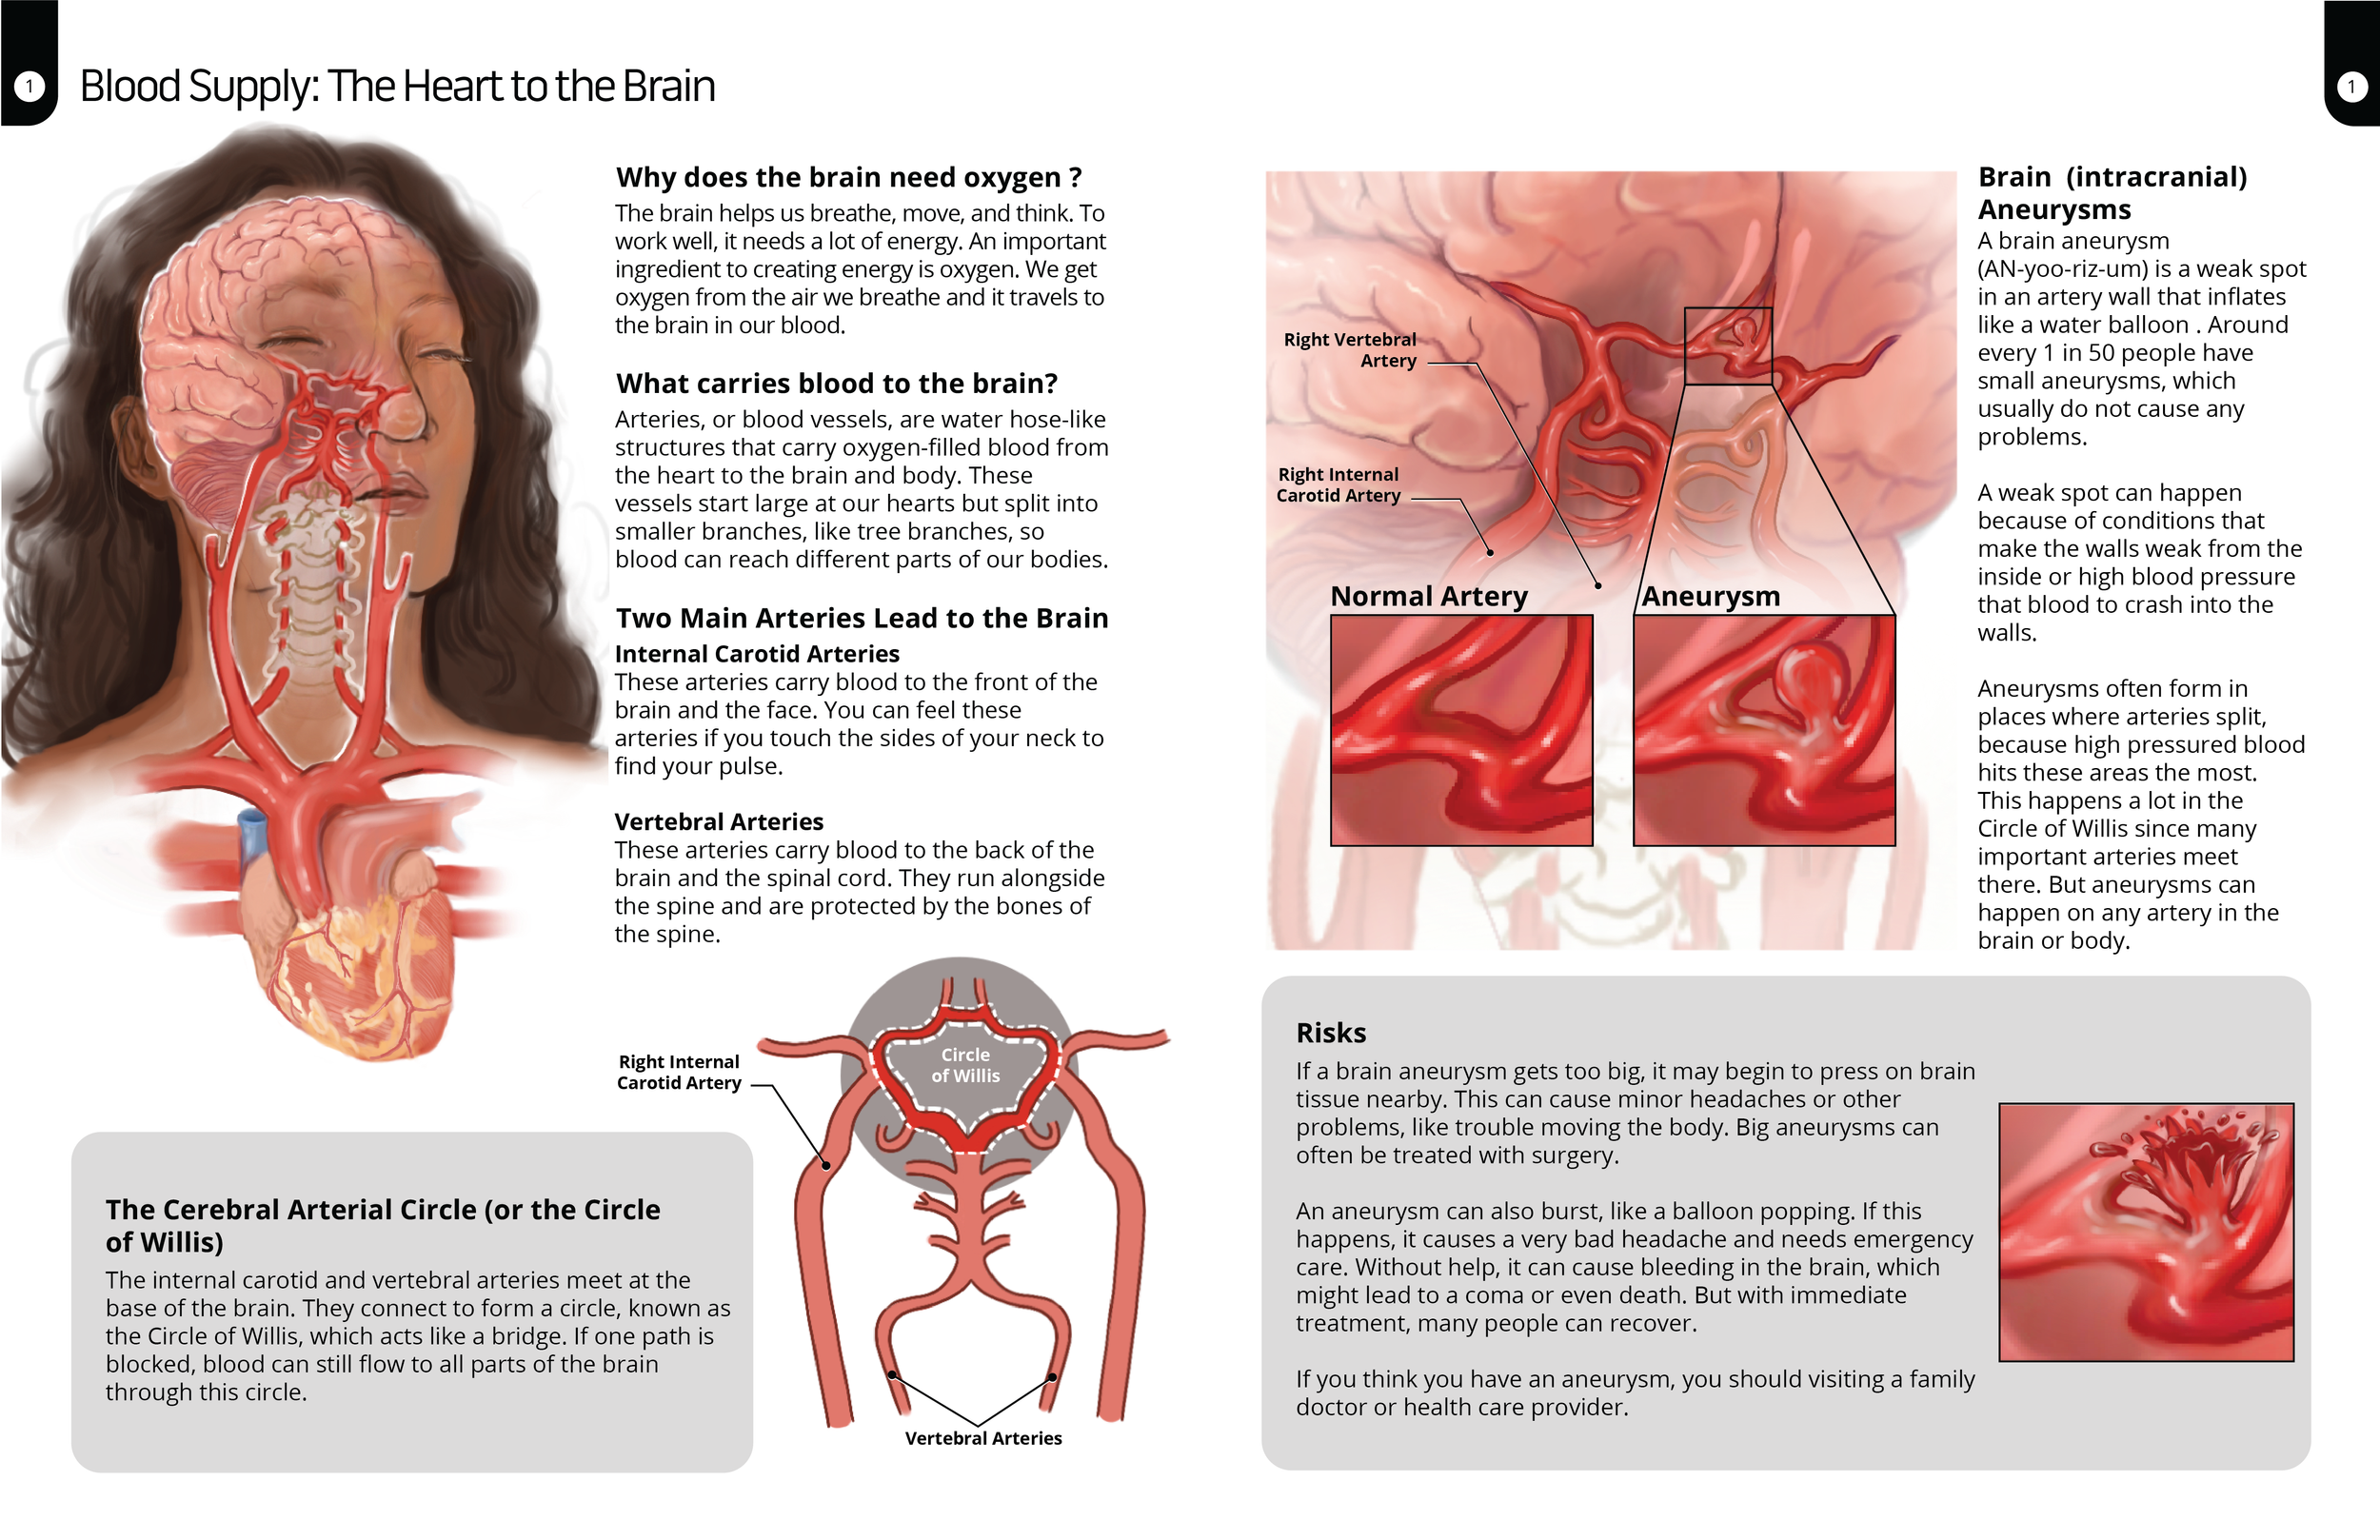

Craniosynostosis Care

Explore a curated collection of our past work, where imagination meets strategy. Each project reflects our drive to deliver thoughtful, effective solutions.

Series: Inclusive Anatomy